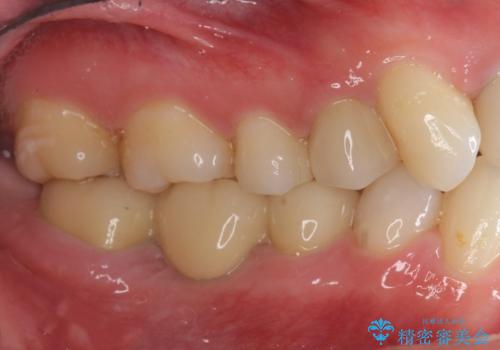

放置した虫歯 ブリッジ治療

- 治療途中の歯を3年放置した結果、ファイバーコア下に虫歯が再発し抜歯を余儀なくされました。

インプラント治療ではなく手術の必要のないブリッジ治療を希望・選択されたので治療を進めます。

最終的なクラウンを入れずコアのまま、仮歯のまま長期間過ごすと虫歯が再発し残すことが難しくなってしまうことがあります。